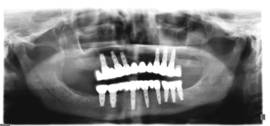

לפנינו עוד מקרה מורכב של שיקום פה מלא למתרפאה כבת 70 אשר כול שינייה עששתיות וניידות ולכן אבודות.

בלסת תחתונה בוצעו 8 שתלים הפעם בשני שלבים ובהפרש של מספר שנים.

ובלסת עליונה 6 שתלים בישיבה אחת מייד לאחר עקירות כל השורשים עם הרמת סינוס סגורה משני הצדדים. השתלים שוקמו בעזרת גשרי חרסינה מאוחה למתכת עם תוצאה אסטטית ותפקודית מעולה.